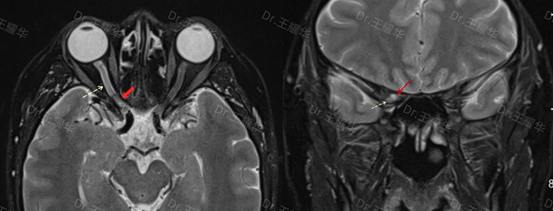

“眼眶增强磁共振发现,患者的右眼视神经管内软组织占位,视神经受压并伴有水肿。” 眼眶眼肿瘤/眼鼻相关专科王耀华副主任医师说,一颗深藏于“眼眶禁区”的视神经管肿瘤,正是窃取李女士光明的“元凶”。

(患者术前检查——红色箭头:视神经管内肿瘤,黄色虚线箭头:受压的视神经)

为何称其为“眼眶禁区”?肿瘤位于眶尖区更靠后的视神经管内,视神经管是眼眶与颅脑交界处的骨性通道,被视神经鞘膜包绕的视神经穿行其中,几乎没有多余空间,且肿瘤与视神经及视神经鞘膜紧密粘连。“就像一根手机充电线,外皮是视神经鞘膜,内部金属导丝是视神经,肿瘤长在‘外皮’里,直接压迫‘金属导丝’。”王耀华解释,若进行手术,术中稍有不慎就可能造成视神经二次损伤、视力完全丧失,甚至引发颅内损伤或感染。因此,该区域曾被视为手术“禁区”。